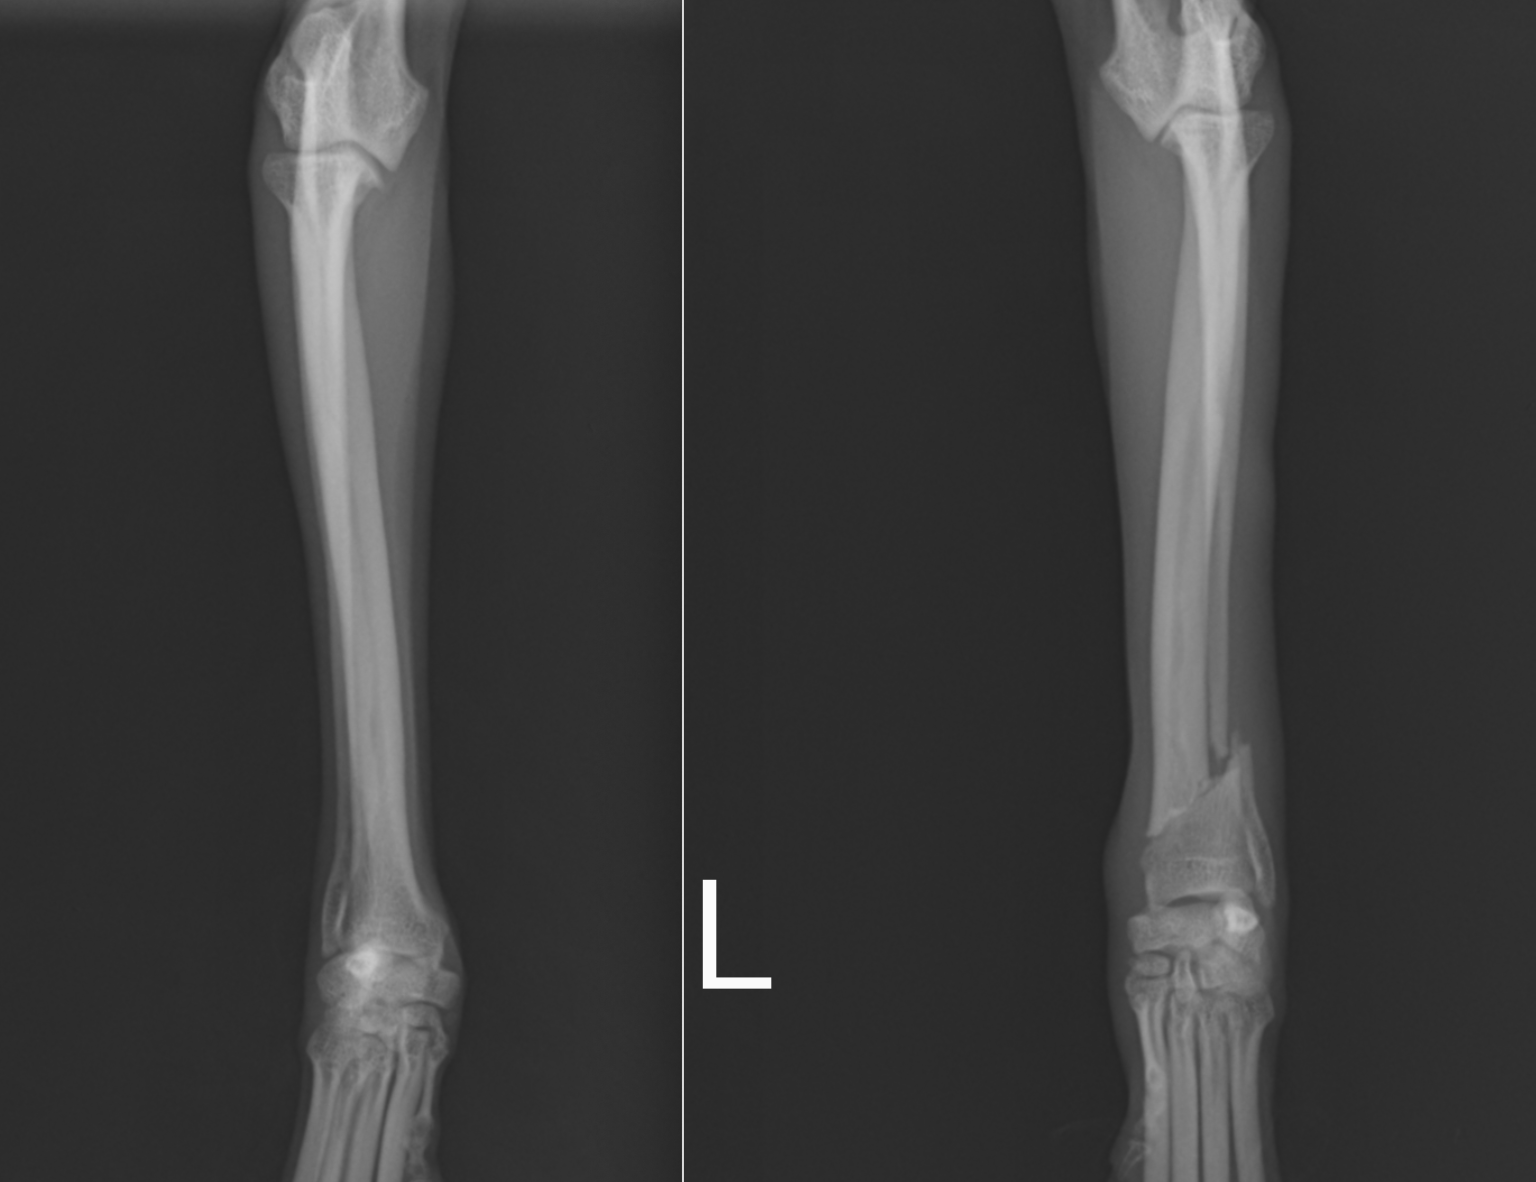

次の症例は11ヶ月のトイプードルで、スリングから飛び降りた後から足をケンケンするということで来院しました。左橈尺骨遠位斜骨折で、2日後に手術を実施しました。遠位骨折の場合尺骨(細い方の骨)には治療を行いませんが、骨折線も綺麗にあっているのがわかります。術後は次の日から足を着くことが可能で、1週間後に帰る時には通常に近い歩様で帰っていきました。その後1週間で抜糸となりますが、そこまでは散歩を5〜10分ほどにしてもらいます。ジャンプや激しい運動はしないでもらっています。その後2週間は散歩を15〜20分、その後1ヶ月は25〜30分で、その頃にプレートを1枚抜去します。

正面から見たレントゲン画像です。

横から見たレントゲン画像です。

術後のレントゲン画像です。足もまっすぐになり、尺骨という骨も綺麗にあっているのがわかります。